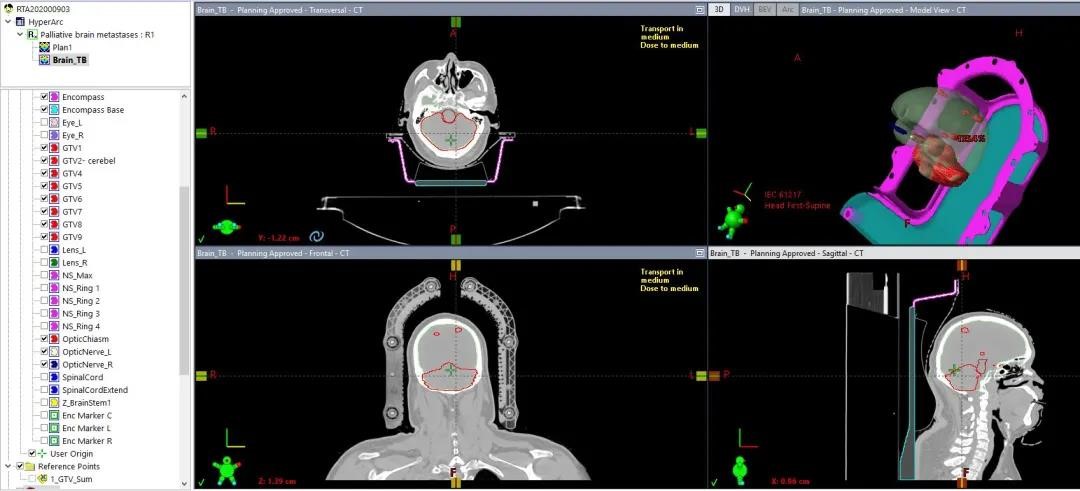

勾画

1、靶区勾画前需进行多模态影像融合

2、Body需要包括面罩和卡扣

3、Encompass床板需与影像对齐

4、靶区和OAR需转换成高精度结构

自动布野

1、TPS根据靶区位置形状自动定义等中心、自动布置非共面旋转弧形射野,物理师根据经验可适当调整

2、TPS可自动优化准直器角度,减少孤岛阻塞、提高治疗效率、降低正常脑组织剂量

3、TPS可用Virtual Dry Run功能进行可视化碰撞检测

02 多发脑转移

肺癌脑多发转移,5个靶点,最大直径3cm,48Gy/12F,

CI:1.14、5mm外跌落到50%处方剂量

HyperArc剂量跌落明显优于传统非共面VMAT治疗,

而且对于多发脑转移,各靶点单独优化,效果更好